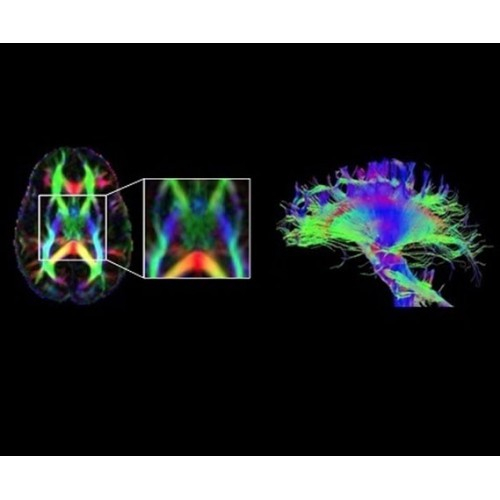

В систему SIGNA PET/MR встроены запатентованные детекторы кремниевого фотоумножителя (SiPM) и сверхчувствительные кристаллические сцинтилляторы на основе лютеция толщиной 25 мм. Благодаря этому обеспечивается исключительная чувствительность и возможность использования времяпролетной диагностики (TOF).

Кроме того, в результате использования технологии TOF и инновационной технологии реконструкции Q.Clear вы сможете добиться прекрасного соотношения сигнал/шум. А благодаря технологии нулевого времени эхо (ZTE) визуализировать костную структуру без ионизирующего излучения. Все эти разработки для улучшения качества сканирования и точности анализа помогут вам использовать весь потенциал ПЭТ/МРТ.

• TurboTOF — инновационная технология позволяет корректировать коэффициент затухания сигнала и минимизировать потери анатомических данных, создавая МР-систему для количественной визуализации.

• Q.Clear — в основу технологии легли накопленные знания о том, как минимизировать помехи при реконструкции и получить четкое изображение. При значительном улучшении качества изображения сохраняется точность расчетов. Сочетание технологии TOF и реконструкции Q.Clear — ваш надежный помощник для получения точных и достоверных данных.

• МРТ с функцией нулевого времени эхо (ZTE) отличается точностью, возможностью персональных настроек и отсутствием ионизирующего излучения. Она приходит на смену традиционному исследованию на основе рентгеновского излучения. МРТ с функцией нулевого времени эхо (ZTE) на базе SIGNA ПЭТ/МРТ является более надежной и быстрой по сравнению с системами, использующими сверхмалое время эхо (UTE).